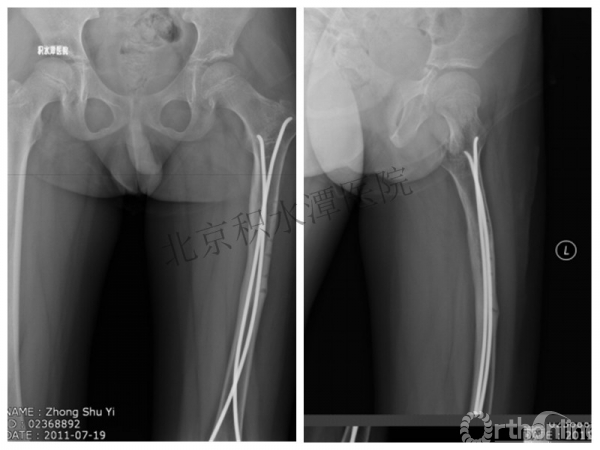

男孩 、5岁,初次骨折于2007年7月。

术后2年→再骨折→再次手术